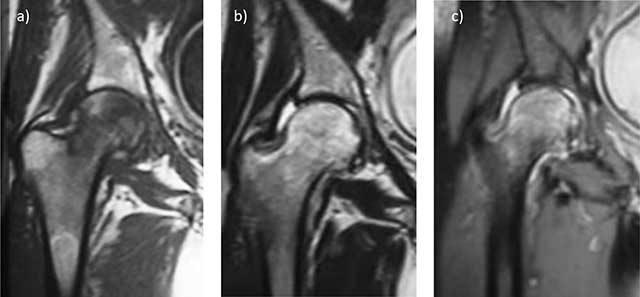

Figure 1

Transient osteoporosis of the right hip; MRI shows diffuse bone marrow edema of the femoral head extending in the femoral neck, with no fracture or osteonecrosis line. T1 spin echo (SE) coronal image a) Shows diffuse low signal of the whole femoral head. SE T2 b) and STIR c) Coronal images show heterogeneously high signal in the same area, with moderate joint effusion.